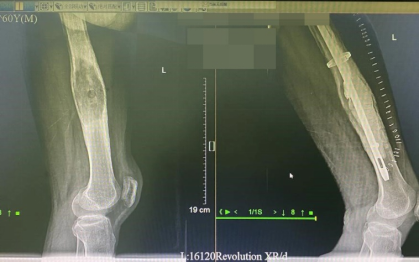

直到近一年来,疼痛越来越剧烈,无法忍受才到南方医科大学中西医结合医院接受全面检查,DR检查结果让人触目惊心:发现左股骨中下段肿瘤,而且肿瘤已经完全把左股骨髓腔给侵蚀掉了。

肿瘤已完全侵蚀左股骨髓腔

这时,莫阿叔的股骨仅剩下一层薄薄的外壳。为了保证术后股骨强度,徐楚江通过置入髓内钉和瘤腔填充骨水泥,填充了肿瘤细胞刮除后留下的巨大空洞。经过7个小时的手术后,莫阿叔的手术顺利完成。

术前(左)与术后(右)对比